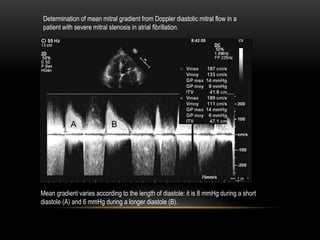

Mean gradient varies according to the length of diastole: it is 8 mmHg during a short

diastole (A) and 6 mmHg during a longer diastole (B).

Determination of mean mitral gradient from Doppler diastolic mitral flow in a

patient with severe mitral stenosis in atrial fibrillation.